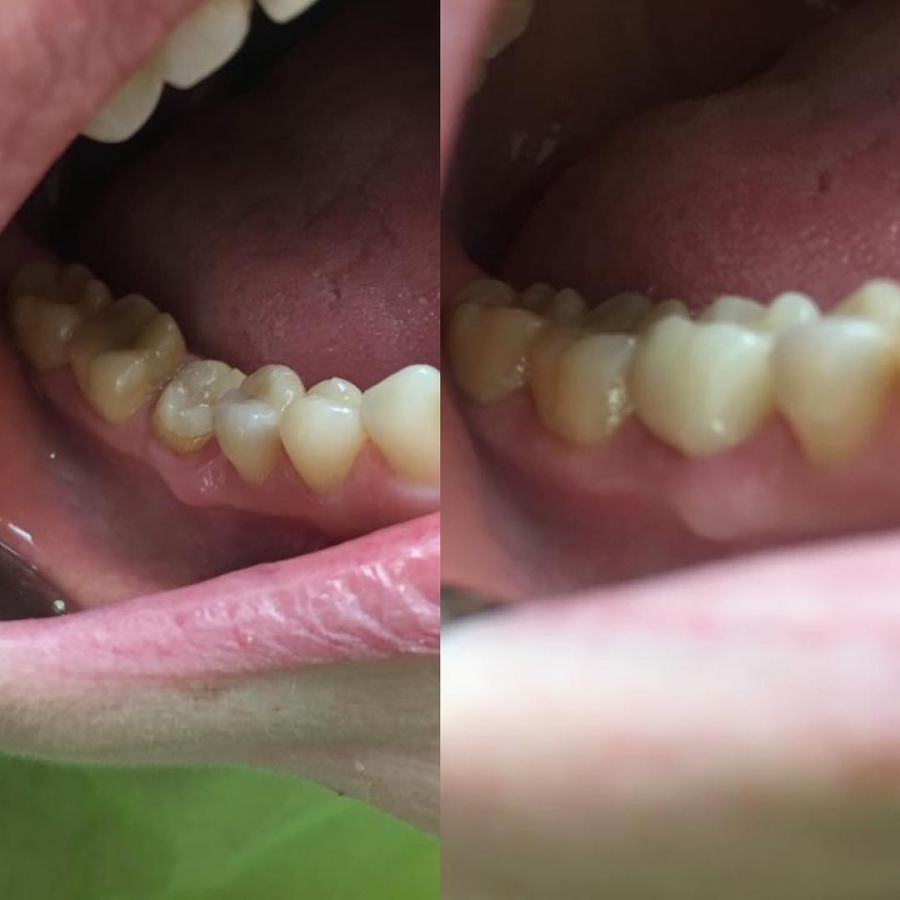

Corona in zirconia su moncone dentale del sesto dente

Preparazione moncone dentale del sesto dente dell'arcata dentale inferiore destra e applicazione di corona in zirconia.